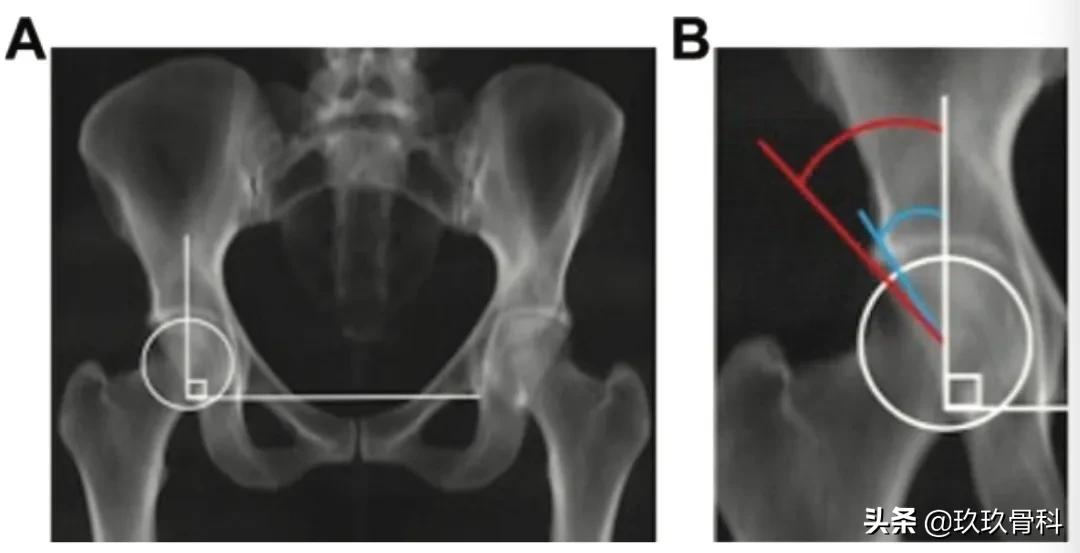

(A)通过CT数据重建的骨盆前后位片。穿过泪滴的水平线表示为标准的骨盆片,垂线经过股骨头中心。(B)放大的股骨头片显示硬化缘LCEA(蓝色,32°)和骨缘LCEA(红色,42°)

(A) 冠状位CT扫描,测量值等于硬化缘外侧中心边缘角(蓝色,32°)。(B) 冠状位CT扫描通过与骨缘外侧中心边缘角相同的最大外侧中心边缘角(红色,42°)。